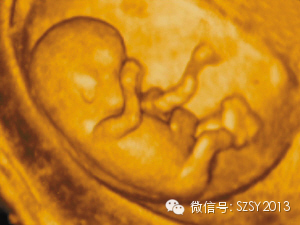

四维彩超就是四维成像技术(4D),能直观、立体显示人体器官的三维结构及动态、实时地观察立体结构,而以往的二维成像技术只能显示人体器官的某一切面。在妇产科方面,四维彩超能立体显示胎儿的颜面部、各器官的发育情况,甚至胎儿在母体里的状态也可以观察到:对胎儿的畸形,如唇裂、腭裂、骨骼发育异常、心血管畸形等能早期诊断。四维彩超是排除胎儿的外观畸形的重要手段,做到及时发现及时纠正。